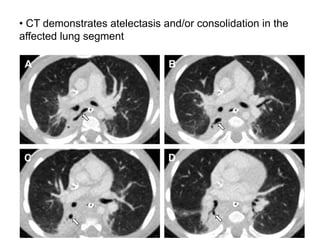

• CT demonstrates atelectasis and/or consolidation in the

affected lung segment